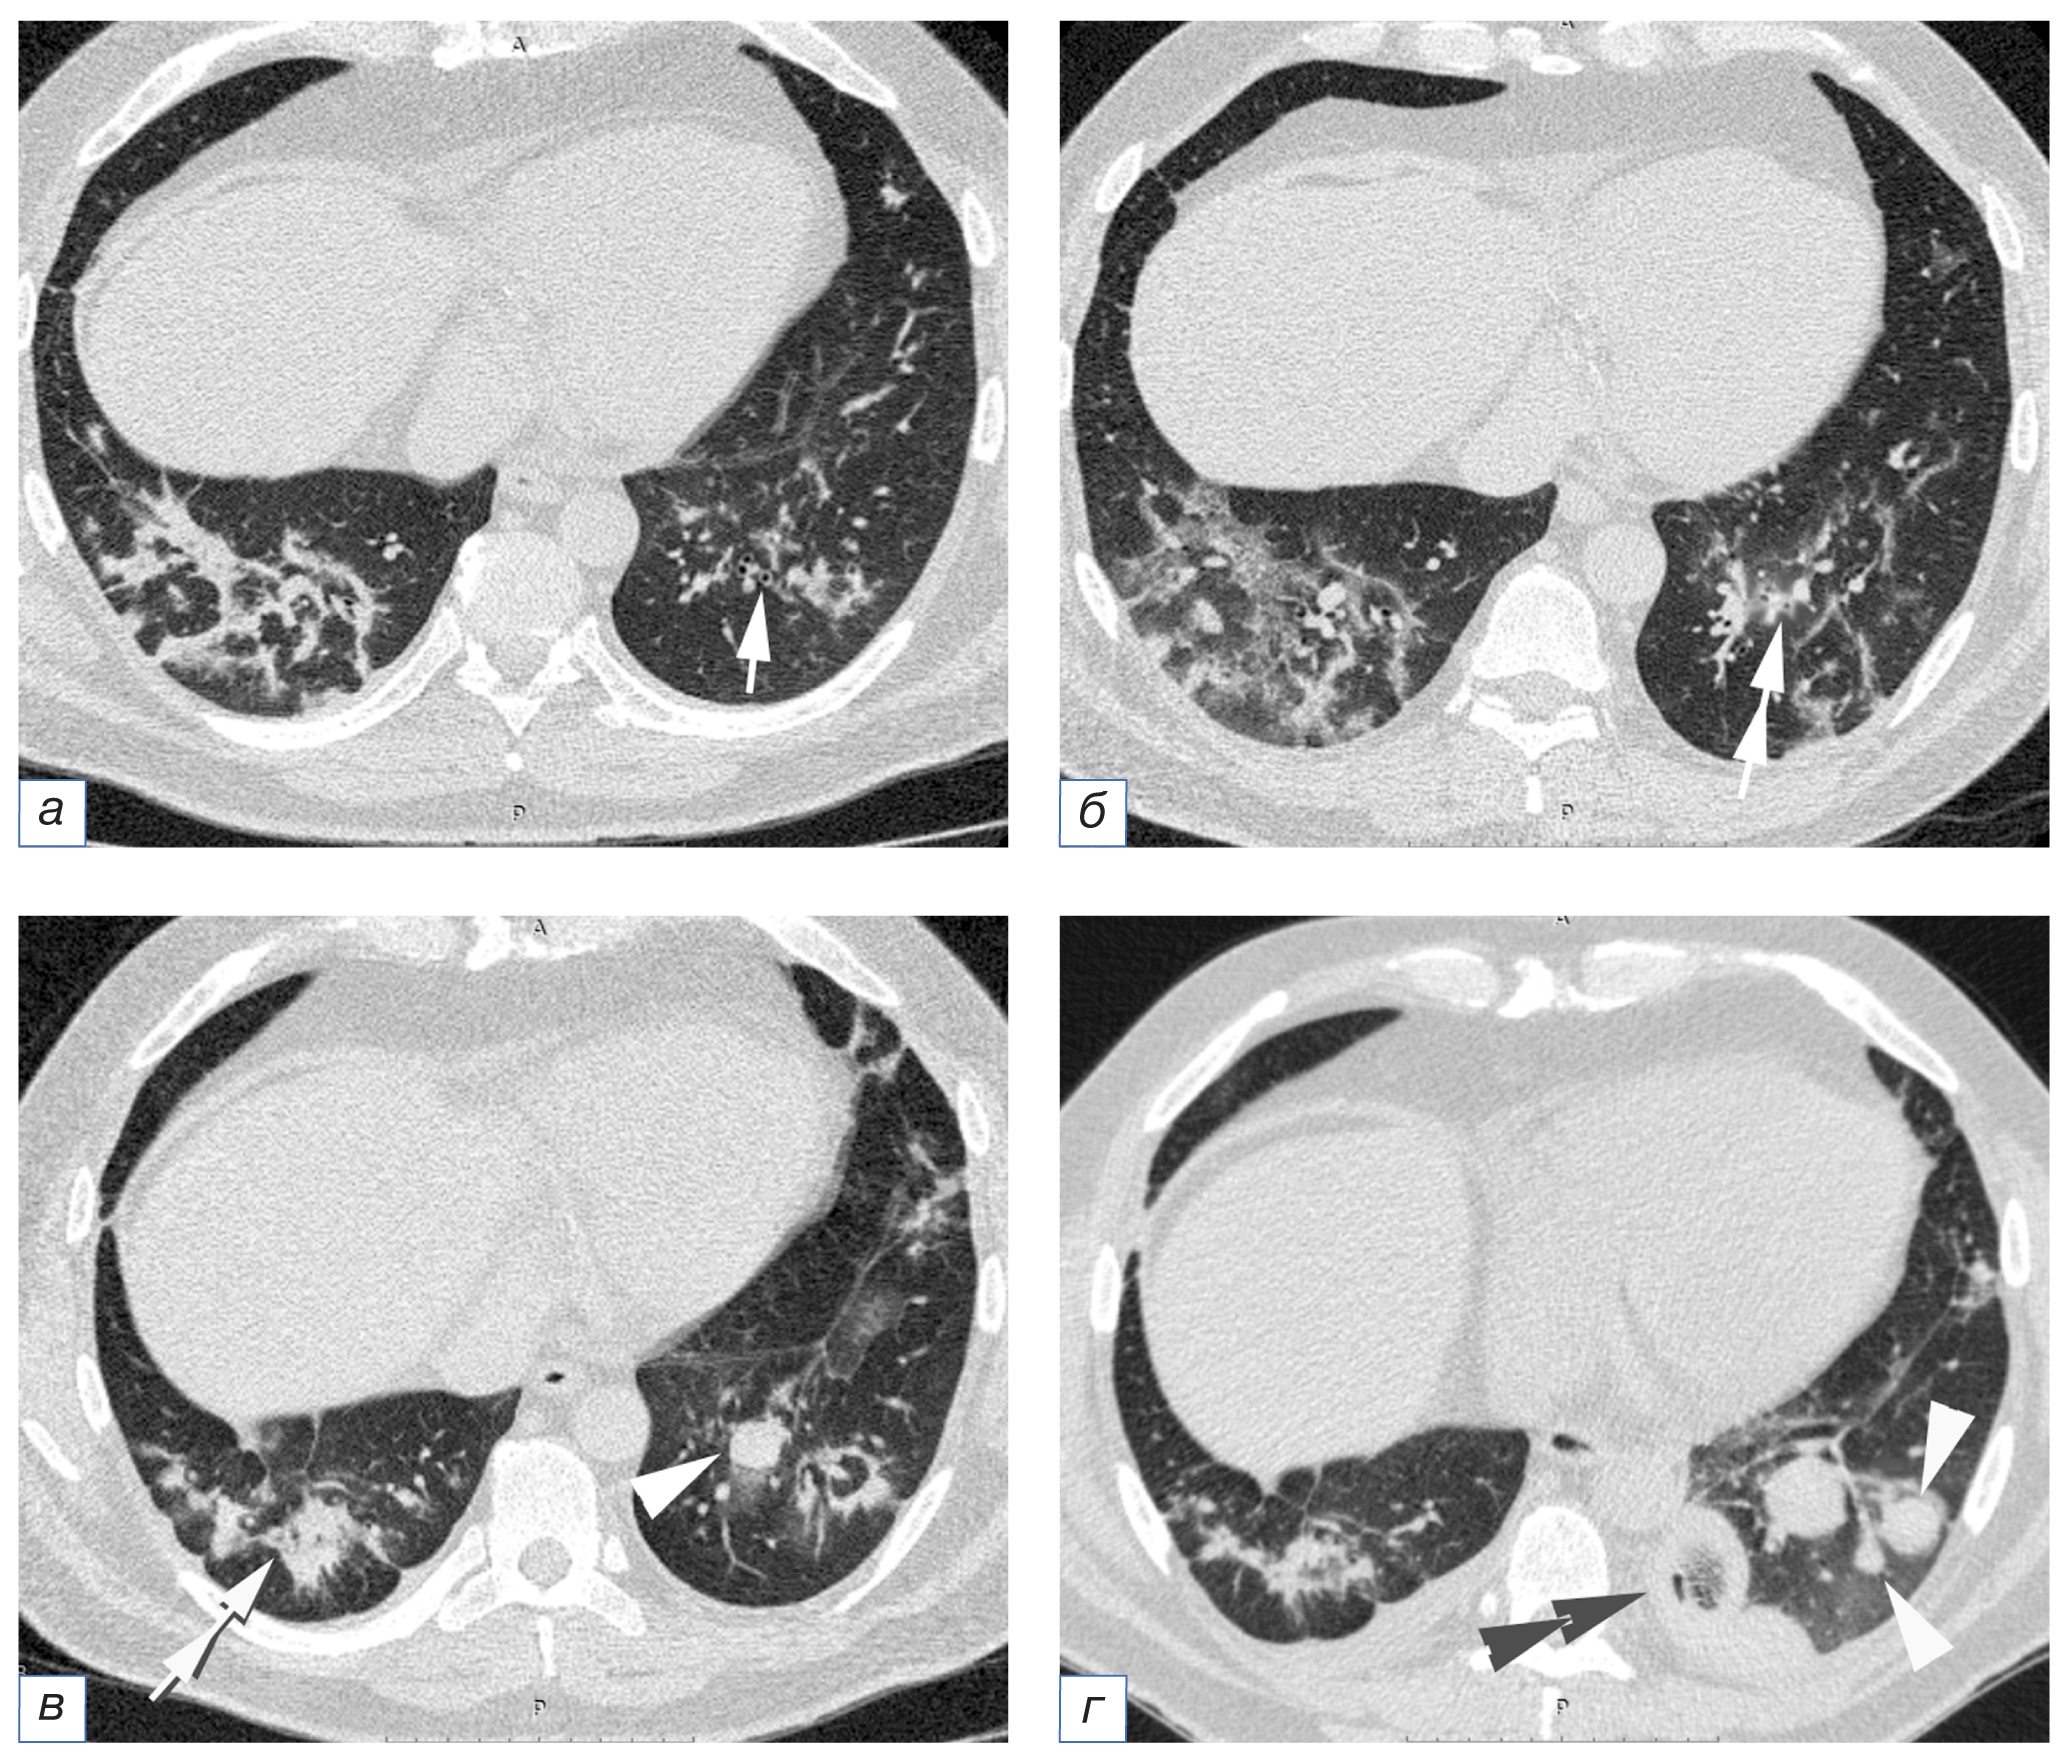

- нодулярный аспергиллёз: перибронховаскулярные уплотнения («перибронхиальные манжеты»), одиночные и множественные очаги, преимущественно внутридольковые и образующие симптом «дерево с набухшими почками», сливаются в более крупные очаги с формированием «микотического шара»; в дальнейшем может сформироваться полость с толстыми неровными стенками, или мицетома (рис. 3);

Рис. 3. Пациент Б., 35 лет, с аспергиллёзом лёгких, возникшем на фоне COVID-19 (COVID-АЛ): а — признаки организующей пневмонии как типичная трансформация вирусного повреждения лёгких, нормальная форма и размеры бронхов нижней доли левого лёгкого (стрелка); б (через 6 дней) — формирование «перибронхиальных манжет» вокруг бронхов нижней доли левого лёгкого (двойная стрелка); в — через 9 дней образование «микотического шара» (треугольная стрелка) и «перибронхиальных манжет» вокруг бронхов нижней доли правого лёгкого; г (через 21 день) — появление новых «микотических шаров» и увеличение размеров ранее выявленного «шара» (треугольные стрелки), формирование симптома «гнездо» в одном из «шаров» (двойная треугольная стрелка).

Fig. 3. Patient B., 35 years old, CAPA: а — signs of organizing pneumonia as a typical transformation of viral lung damage, the normal shape and size of the bronchi of the lower lobe of the left lung (arrow); б — 6 days after, the formation of "peribronchial cuffings" around the bronchi of the lower lobe of the left lung (double arrow); в — 9 days after, the formation of a "mycotic ball" (triangular arrow) and "peribronchial cuffings" around the bronchi of the lower lobe of the right lung; г — 21 days after, the appearance of new "mycotic balls" and an increase in the size of the previously identified ball (triangular arrows), the formation of a "bird’s nest" sign in one of the balls (double triangular arrow).